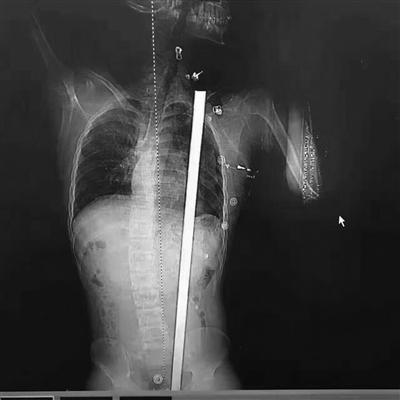

拍片顯示患者體內的鋼筋

“看到CT報告,我們發(fā)現鋼筋直達肩胛”。徐進宇說,從報告上看,鋼筋是從肛門旁進入,穿過腹部和胸部,所幸是從脾、胃、腎中間穿過,和心臟擦過,而且沒有傷及大血管。徐主任說,小楊非常幸運,這根鋼筋的走線都沒有觸碰到關鍵要害,如果傷到了致命血管,勢必造成大出血,病人往往都等不及送醫(yī)。